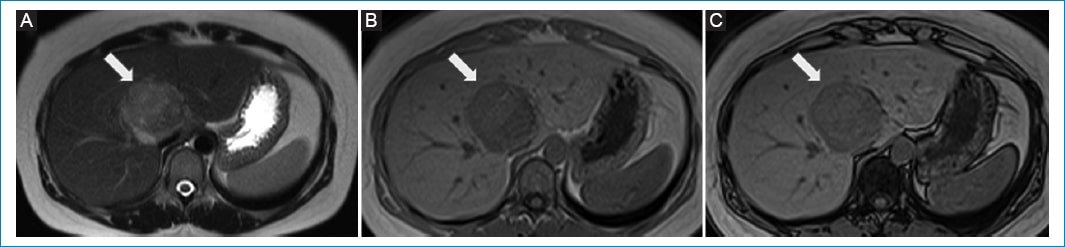

Presentamos el caso de una mujer de 34 años, sin antecedentes médicos relevantes, que fue remitida a nuestro centro por el hallazgo incidental de un tumor hepático en una ecografía debido a dolor abdominal. Se realizó una resonancia magnética (RM) hepática con contraste endovenoso en nuestro centro, que mostró una masa heterogénea en el segmento VIII-IV de 64 x 54 mm, ligeramente hipointensa en T1, ligeramente hiperintensa en T2, con restricción en difusión y realce heterogéneo con el contraste endovenoso en la fase arterial y lavado en la fase tardía (Fig. 1–Fig. 3). No se observó infiltración de estructuras vasculares. Se interpretó como una lesión maligna, pudiendo corresponder a un carcinoma hepatocelular (HCC) o a un adenoma maligno.

Figura 1. RM hepática. Axial T2 (A), T1 en fase (B) y T1 fuera de fase (C) muestran un tumor bien circunscrito en los segmentos VIII-IV, con ligera hiperintensidad en T2 y la misma señal hipointensa en las secuencias ponderadas en T1 fase y fuera de fase (flechas).